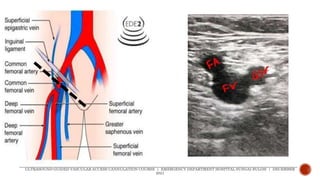

 Common femoral artery

 midpoint of inguinal

ligament

 Common femoral vein

 medial to common

femoral artery

 Common femoralartery  midpoint of inguinal ligament  Common femoral vein  medial to common femoral artery ULTRASOUND-GUIDED VASCULAR ACCESS CANNULATION COURSE | EMERGENCY DEPARTMENT HOSPITAL SUNGAI BULOH | DECEMBER 2021